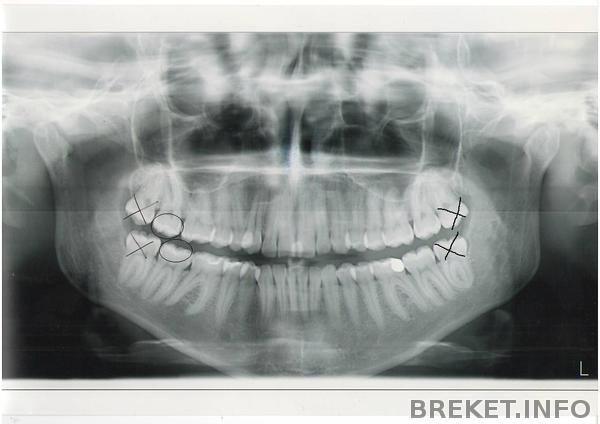

Мне удалили все восьмерки в два приема с разницей примерно в месяц прошлым летом. Я долго не чувствовала боли во рту ВООБЩЕ! Постоянно прикусывала себе язык в первые пару месяцем и понимала это только когда чувствовала вкус крови во рту. Постепенно болевая чувствительность вернулась (примерно к ноябрю), но, назовем ее так, "тактильная" чувствительность языка не вернулась до сих пор, уже спустя год. До сих пор, когда ортодонт просит меня провести языком по брекетам с целью выявить места, которые выпирают и могут натирать, я не чувствую ничего. То есть я понимаю, что у меня что-то на зубах, но настолько подробно прочувствовать не могу. То же самое с деснами. Когда через месяц после удаления я пожаловалась на это хирургу, удалявшему зубы, он показал мне мой снимок, где было видно, что корень одной из восьмерок касается (боюсь ошибиться с названием) нервного канала и оттого у меня такая реакция произошла. Пообещал что со временем чувствительность восстановится, но вот прошел уже год, а как-то не очень)) Хотя, я не жалуюсь - уже совершенно привыкла и неудобств мне это не доставляет. Я уже 10 месяцев ношу брекеты и у меня ни разу не болели зубы. Разве что чуть-чуть в первые дни после активации. Ортодонт говорит, что из-за моей сниженной болевой чувствительности челюсти я избежала этих прелестей брекетоношения) Может так оно и есть.

На снимке у меня видно, что корень восьмерки рядом с нервным каналом.